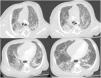

Ante la sospecha de enfermedad pulmonar difusa, como es en nuestro caso, la Sociedad Española de Neumología Pediátrica recomienda3 ampliar el estudio con la realización en primer lugar de tomografía computarizada (TC) torácica. En nuestro caso, ante la persistencia de taquipnea e hipoxemia, se realiza TC torácica a los 26 días de vida que muestra hallazgos compatibles con patrón intersticial (fig. 1).